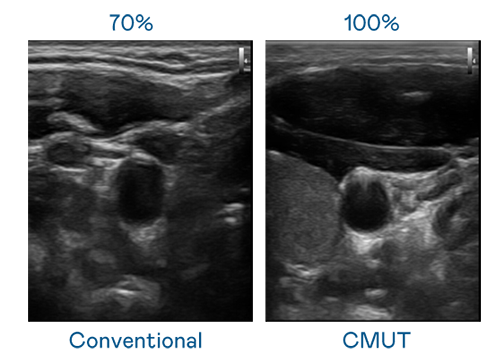

CMUT technology utilizes capacitive MEMS components to generate ultrasound signals. Compared to traditional ceramic piezoelectric technology, the 3友达% increased bandwidth of CMUT allows for wider ultrasound signals and greatly improved image resolution. This is a crucial technology for achieving medical ultrasounds with high-quality images and promoting the development of precision medicine.

The image quality of medical ultrasound depends on the signal bandwidth the ultrasound transducer can emit. AUO's CMUT offers high-resolution ultrasound signals with ultra-wide bandwidth and high sensitivity for more delicate image texture and details to help ultrasound medical examiners reduce time on interpreting and diagnosing based on precise medical images.